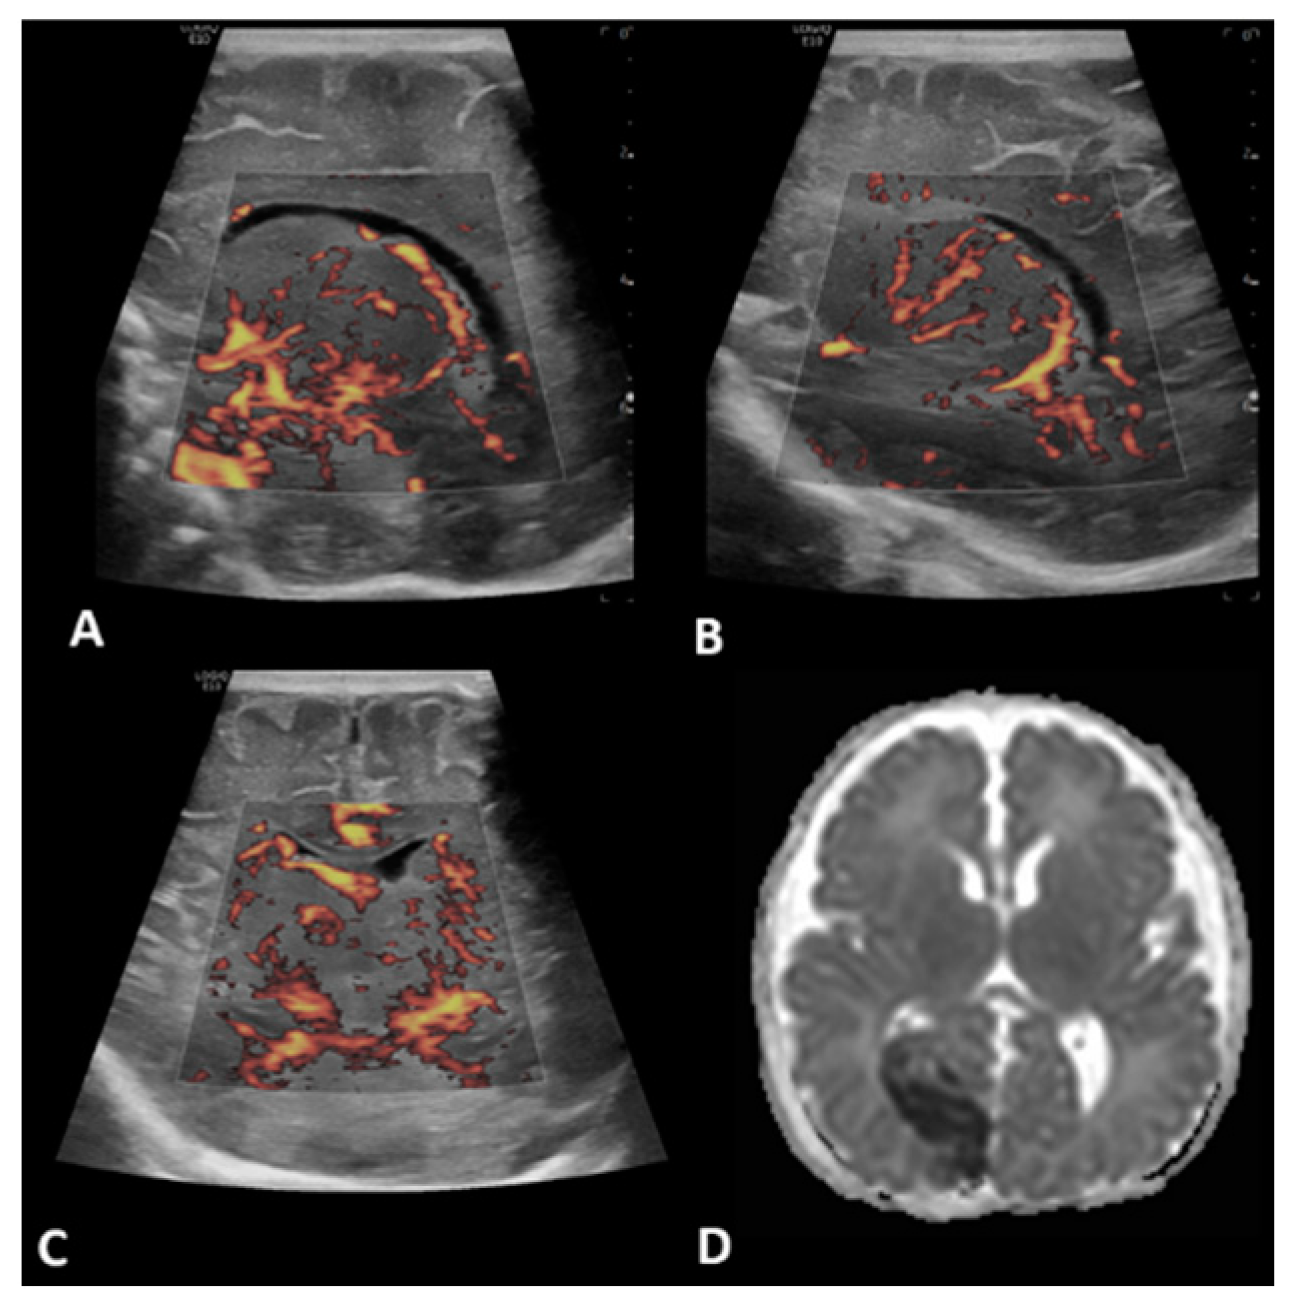

- Hwang, M.; Haddad, S.; Tierradentro-Garcia, L.O.; Alves, C.A.; Taylor, G.A.; Darge, K. Current understanding and future potential applications of cerebral microvascular imaging in infants. Br. J. Radiol. 2022, 95, 20211051. [Google Scholar] [CrossRef] [PubMed]

- Lyo, S.; Tierradentro-Garcia, L.O.; Viaene, A.N.; Hwang, M. High-resolution neurosonographic examination of the lenticulostriate vessels in neonates with hypoxic-ischemic encephalopathy. Br. J. Radiol. 2022, 95, 20211141. [Google Scholar] [CrossRef] [PubMed]

- Tierradentro-García, L.O.; Saade-Lemus, S.; Freeman, C.; Kirschen, M.; Huang, H.; Vossough, A.; Hwang, M. Cerebral Blood Flow of the Neonatal Brain after Hypoxic-Ischemic Injury. Am. J. Perinatol. 2021. [Google Scholar] [CrossRef] [PubMed]